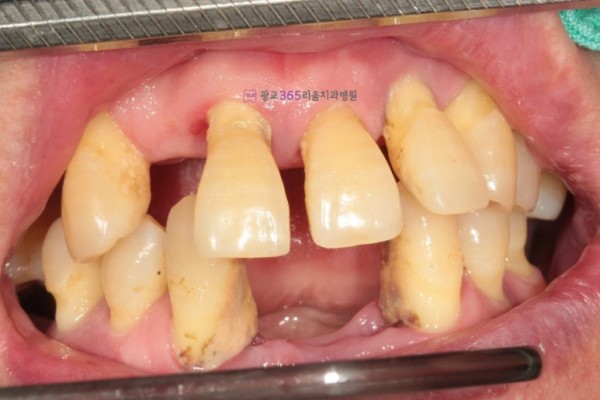

임플란트 | 치아가 거의 없었는데 [치료 후 삶의 질이] [달라졌어요.]